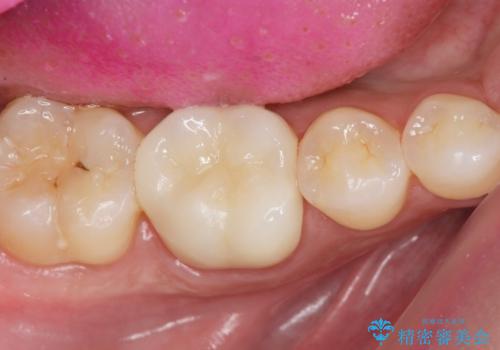

3. 放置してしまった虫歯の治療の治療後